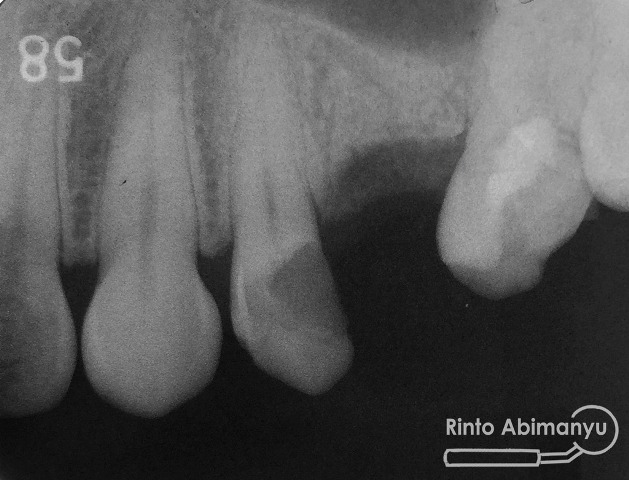

dan ini ronsennya…

Ok dari keadaan klinis saya lihat gigi 24 dengan karies yang cukup dalam dan dinding distal sudah tidak ada, dari ronsen terlihat kavita sudah mendekati kamar pulpa. Ketika dilakukan perkusi tidak ada respon, juga ketika dilakukan tes respon dingin juga tidak ada reaksi…